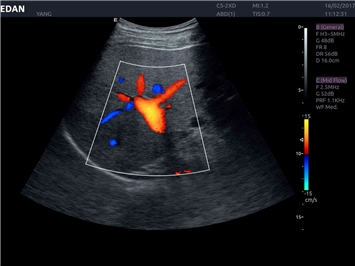

Цветовой допплер:

Да

Высокочастотный импульсный допплер:

• Повышенная чувствительность при цветовом допплеровском картировании